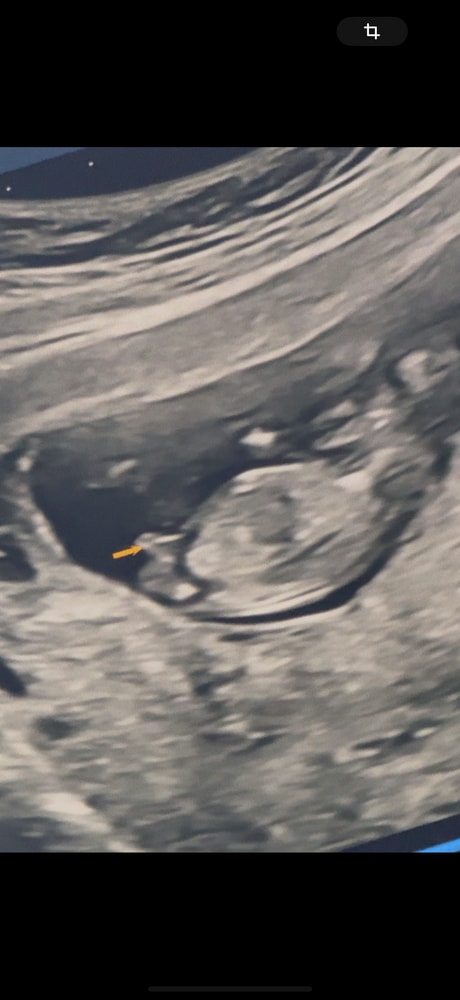

Всем здравствуйте! Сегодня была на первом скрининге в 13 недель и 4 дня. Очень переживала, но с ребенком всё отлично! К моему удивление, сказали, что пол уже виден. Спросили меня хочу ли я знать, и я конечно сказала, что хочу. Будет мальчик. Я даже переспросила, точно ли это, ведь на таком маленьком сроке могут быть погрешности, но мне ответи

это правда половой орган мальчика ?)

не пуповина или что-то другое?

Но сама узистка сказала и вот показала что мальчик скорее всего …Но 100 % не дала

у кого так торчал при Мальчике ?